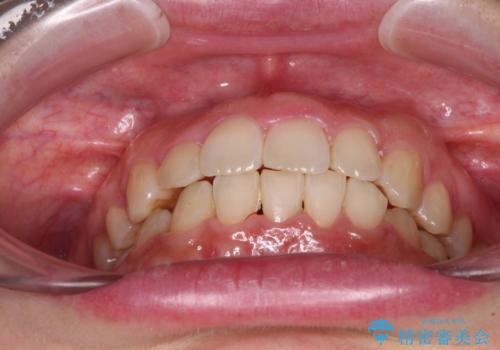

- 右上の八重歯と、左下八重歯を抜いてしまったことを気にして来院された患者様です。

下顎は既に犬歯を1本抜歯しているため、上顎右側第一小臼歯を抜歯し、ワイヤー装置にて歯列を整えることとしました。

変則的な抜歯となるため、正中と人中がずれる可能性がありましたが、仕上がりは上下正中を揃えることができました。